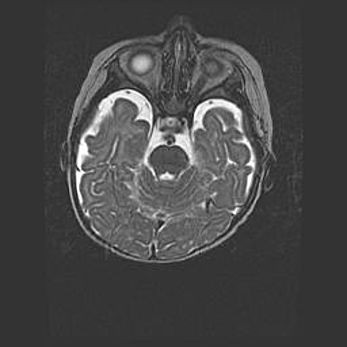

Мальформация Денди-Уокера. Киста задней черепной ямки.

Агенезия мозолистого тела.

Возраст: 2,5 месяца

Вес: 2420 г

Пол: женский

Окружность головы: 37 см

Срок гестации: 32 недели

Мальформация Денди—Уокера — редкий вид патологии ЦНС, представляющий собой врожденный порок развития каудального отдела ствола и червя мозжечка, ведущий к неполному раскрытию срединной (Мажанди) и латеральных (Лушка) апертур IV желудочка мозга. Для этогно синдрома характерна триада симптомов: гипотрофия червя мозжечка и/или полушарий мозжечка, кисты задней черепной ямки, гидроцефалия различной степени. В 70% случаев порок сочетается и с другими аномалиями головного мозга, в частности с агенезией мозолистого тела.